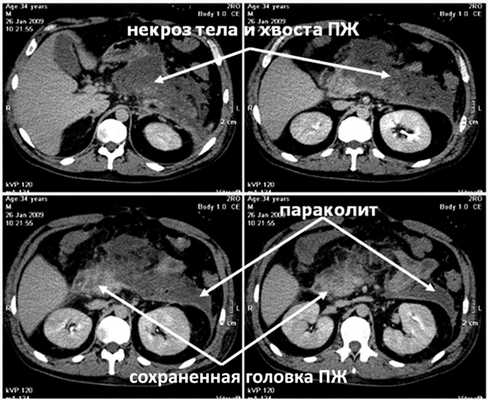

Выполнена КТ с внутривенным контрастным усилением (рис. 3, а), Рисунок 3. Компьютерные томограммы больного Б. а - при поступлении. Субтотальный некроз ПЖ, параколит слева. при которой диагностирован полный некроз тела и хвоста ПЖ с сохранением жизнеспособности только ее головки, парапанкреатит, левосторонний параколит, распространяющийся до подвздошной области.

К середине этих же суток на фоне быстрого повышения ВБД до 28 мм рт.ст., что сопровождалось еще более значительным увеличением объема живота, возникли анурия и гипотензия с АД 75/40 мм рт.ст. Начато внутривенное введение дофамина в увеличивающихся дозах, максимально 12 мкг на 1 кг массы тела в 1 мин - без эффекта, затем - адреналина в дозе 0,15 мг на 1 кг массы тела в 1 мин, чем удалось стабилизировать АД на уровне 125/75 мм рт.ст. Проявления дыхательной недостаточности значительно усугубились - на фоне принудительной исскуственной вентиляции легких 100% кислородом индекс оксигенации снизился до критического уровня, составив 115 (нижняя граница нормы 350). Уровни мочевины и креатинина в сыворотке крови в это же время повысились до 32 ммоль/л и 298 мкмоль/л соответственно. Таким образом, на 3-и сутки заболевания и лечения у больного с субтотальным некрозом ПЖ и обширным некрозом забрюшинной жировой клетчатки отмечена развернутая картина прогрессирующей ПОН с недостаточностью функции четырех органов или систем (легких, почек, головного мозга, сердца и сосудов), что произошло на фоне ВБГ III степени. Диагностирован АКС, в связи с чем пациенту экстренно выполнили фасциотомию путем рассечения апоневроза по белой линии живота от мечевидного отростка до лонного сочленения без вскрытия брюшины из двух небольших кожных разрезов длиной по 3 см. Через 30 мин после операции ВБД снизилось с 28 до 19 мм рт.ст., а через 4 ч - до 14 мм рт.ст., после чего восстановился нормальный темп диуреза, показатели гемодинамики позволили прекратить инфузию адреналина, была уменьшена дыхательная поддержка. На 2-е сутки после операции ВБД снизилось до 8 мм рт.ст., на 3-и сутки - до 5 мм рт.ст. и впоследствии не повышалось. Суточный диурез составлял 2-2,5 л, показатели мочевины и креатинина крови к 5-м суткам после декомпрессии брюшной полости снизились до нормы. Постепенно индекс оксигенации повысился до нормальной величины, на 6-е сутки после операции больной был переведен на режим вспомогательной вентиляции, а через 10 сут после фасциотомии - на самостоятельное дыхание. Швы с ран сняты в срок, зажили первичным натяжением. Фазу инфекционных осложнений ОДП удалось миновать путем комплексной профилактики, включающей внутривенное введение тиенама в дозе 3 г в сутки, энтеральное зондовое питание и селективную деконтаминацию желудочно-кишечного тракта. На 14-е сутки лечения больной переведен в хирургическое отделение. Необходимости выполнения чрескожных диагностических и лечебных вмешательств под контролем УЗИ, а также хирургической некрсеквестрэктомии не возникло. В области некротизированных тела и хвоста ПЖ образовалась острая псевдокиста размером 17×7×7 см, параколит регрессировал (см. рис. 3, б). Рисунок 3. Компьютерные томограммы больного Б. б -перед выпиской. Через 29 сут лечения больной был выписан.